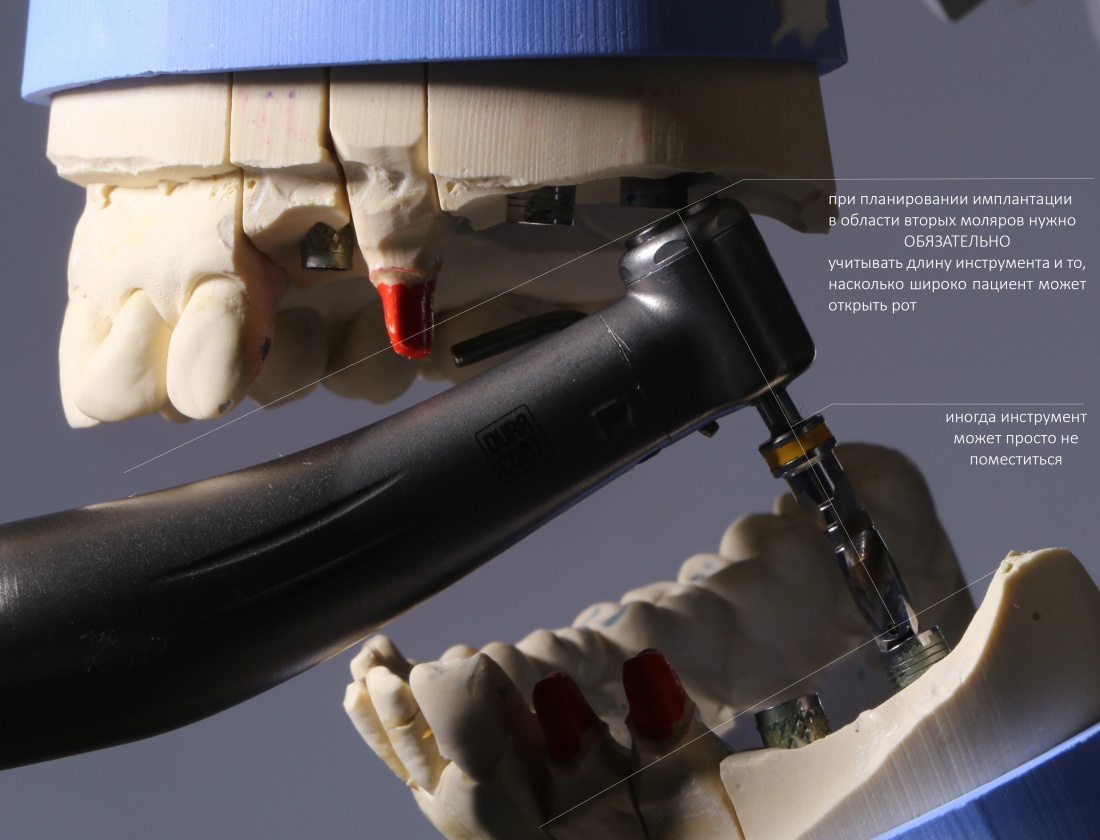

НО! Планируя операцию в области седьмых зубов, либо при затрудненном открывании рта, учитывайте возможность завести инструменты в область имплантации. В таких случаях, возможно, имеет смысл склоняться к использованию имплантатов длиной не более 10 мм, ибо с большей длиной просто будет сложнее работать: